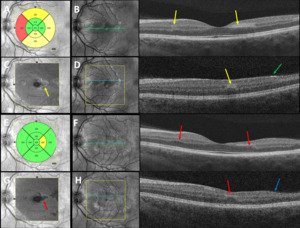

Best-corrected visual acuities were 20/20-1 right eye and 20/20-1 left eye. Pupils were equally round and reactive to light without an afferent pupillary defect. Extraocular movements were smooth and full in both eyes. Confrontation visual fields were full to finger counting in each eye. Amsler grid testing revealed a small area of metamorphopsia temporal to fixation in the right eye and small areas of metamorphopsia nasal and superotemporal to fixation in the left eye. Red cap testing was equal between the eyes. Slit lamp examination of the anterior segment was unremarkable in both eyes. Intraocular pressures by Goldmann applanation tonometry measured 14 mm Hg in each eye. Dilated fundus examination revealed a cup-to-disc ratio of 0.25 in each eye with well-perfused neural retinal rim tissue without edema or pallor. Examination of the posterior pole revealed mild retinal whitening superotemporal to the fovea in both eyes, a cotton wool spot in the inferior nasal arcade and a cotton wool spot in the inferior temporal arcade of the right eye, and 2 cotton wool spots in the superior temporal arcade of the left eye (Figure 1). The arterial-to-venous ratio was 2/3 in both eyes with no vascular tortuosity and no visible emboli. The peripheral retina was flat without holes, tears, or breaks in both eyes. Optical coherence tomography of the retinal nerve fiber layer revealed thick retinal nerve fiber relative to the normative database (not indicative of subclinical edema but rather due to his young age) inferiorly and nasally in both eyes with average retinal nerve fiber layer thickness of 127 microns in the right eye and 123 microns in the left eye (Figure 2). Optical coherence tomography showed central subfoveal thickness of 275 microns in the right eye (Figure 3A) and 271 microns in the left eye (Figure 4A). There were parafoveal hyperreflective bands in the inner nuclear layer worse in the right eye (Figure 3B) compared with the left eye (Figure 4B). En face optical coherence tomography at the level of the mid-retina showed patchy hyperreflectivity worse in the right eye (Figure 3C) compared with the left eye (Figure 4C), which corresponds to the inner nuclear layer hyperreflectivity on cross-section. Interestingly, in this case, there is also hyperreflectivity of the internal limiting membrane superotemporal to the fovea in both eyes (Figures 3D and 4D, right and left eye, respectively) that corresponds to the areas of retinal whitening seen on fundoscopy. The superficial capillary plexus on optical coherence tomography angiography showed an abnormal foveal avascular zone with small patches of capillary dropout worse in the left eye (Figure 5C) compared with the right eye (Figure 5A); the deep capillary plexus showed multifocal ovoid areas of signal attenuation due to capillary dropout in both eyes (Figures 5B and 5D, right and left eye, respectively).

He was monitored at 4-week intervals but was lost to follow-up after the 3-month visit. Visual acuity improved to 20/20 in each eye at the 1-month follow-up and remained stable throughout the clinical course. Despite this, small areas of metamorphopsia paracentrally worse in the left eye compared with the right eye persisted on Amsler grid testing. Humphrey visual field 10-2 Swedish Interactive Thresholding Algorithm Standard was performed at the 2-month follow-up and confirmed paracentral defects worse in the left eye than in the right eye (Figure 6). At the 3-month follow-up, there was resolution of the retinal whitening and cotton wools spots and near resolution of the paracentral acute middle maculopathy. Optical coherence tomography showed central subfoveal thickness of 262 microns in the right eye (Figure 3E) and 252 microns in the left eye (Figure 4E). There was parafoveal inner nuclear layer thinning worse in the right eye (Figure 3F) compared with the left eye (Figure 4F). En face optical coherence tomography at the level of the mid-retina showed multifocal patchy hyporeflectivity worse in the right eye (Figure 3G) compared with the left eye (Figure 4G), which corresponds to the inner nuclear layer thinning on cross-section. There is also inner retinal thinning in both eyes supertemporal to the fovea (Figures 3H and 4H, right and left eye, respectively) that correspond to the previous areas of internal limiting membrane hyperreflectivity. The superficial capillary plexus on optical coherence tomography angiography was unchanged from the initial presentation in the right eye (Figure 5E) but showed worsening of the abnormal foveal avascular zone with patches of capillary dropout in the left eye (Figure 5G); the deep capillary plexus showed worsening of the multifocal ovoid areas of signal attenuation due to capillary dropout in both eyes (Figure 5F and 5H, right and left eye, respectively).